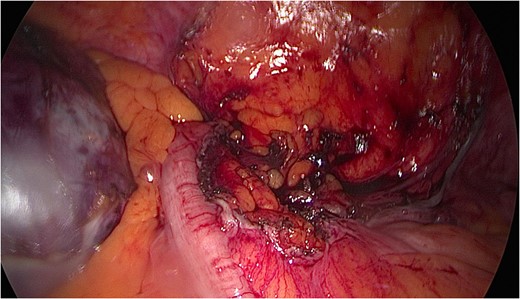

A mesenteric cyst is rare intra-abdominal pathology, with little literature to guide us on how to diagnose and manage it. We report the incident of a 57-year-old female who had an incidental finding of a sigmoid mesenteric cyst whilst undergoing an operation under the care of the Gynaecologists. A computed tomography scan and a flexible sigmoidoscopy followed to help diagnose the lesion as a cyst. A month later the 10 × 15 cm2 cyst was excised laparoscopically with no complications.

The rest of the abdominal cavity was washed with normal saline and closed. Since, the patient has made a full recovery and is completely symptom free. The histology report suggests the mass to be a borderline mucinous cystadenoma with either ovarian or appendiceal origin.